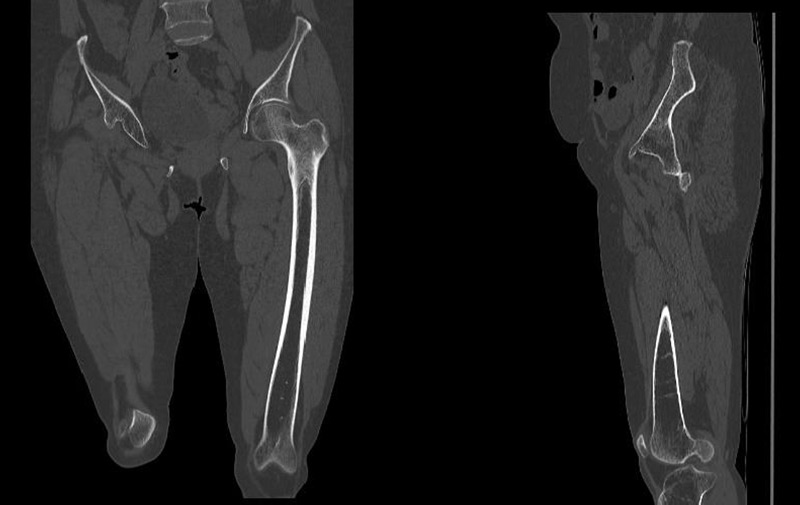

Pre-operative X-rays and CT-scan

Management of a hip dysplasia in a middle-aged woman:  Pre-operative X-rays and CT-scan